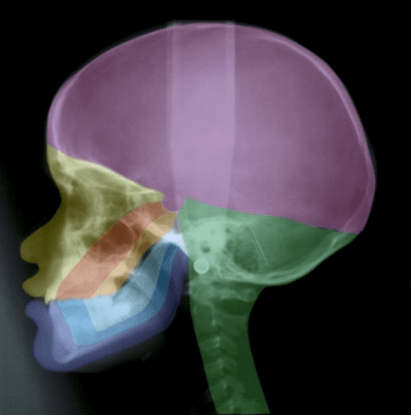

Figure 1: A profile radiograph coloured according to craniofacial fields with different embryological origins. The fields in the maxillary region are: fronto-nasal field (yellow), maxillary field (red) and palatal field (orange). In the mandible the different fields are marked blue. The occipital field is marked green and the theca region purple.

In many genetic studies, such as on Meckel-Gruber syndrome, it can be difficult to define borders between developmental fields. It is only possible to describe where the phenotypic deviations are. It is characteristic for Meckel-Gruber fetuses that they often have 6 fingers and 6 toes, and extensive cranial and neurological malformations in the occipital region including malformed notochordal remnants in the posterior sella wall [126, 127]. Figure 1 depicts a short summary of the developmental borders observed in the profile view of the cranium and cervical spine, as reported in Section 1. In Figure 2 the central nervous system is inserted in the drawing, demonstrated in (Figure 1).

Figure 2: The profile radiograph of the craniofacial fields demonstrated in Figure 1, now with insertion of the brain: H (cerebral hemispheres), D (diencephalon with an extension, infundibulum cerebrii to the sella turcica, where it forms the neuro-pituitary gland), M (metencephalon), BS (brain stem including the pons and cerebellum) and S (spine). Note that the fossa cranii anterior supports the frontal hemispheres and that the green fossa cranii posterior encircles mainly the cerebellum and pons.